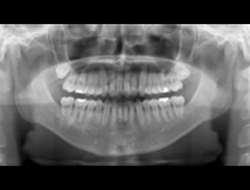

前歯のガタガタと口元の突出感を改善したいと言われました。

口元の突出感の改善には抜歯が必要となり、上下左右の計4本を抜歯しています。治療後は抜歯した隙間を使って配列して、閉じることで口元を入れました。